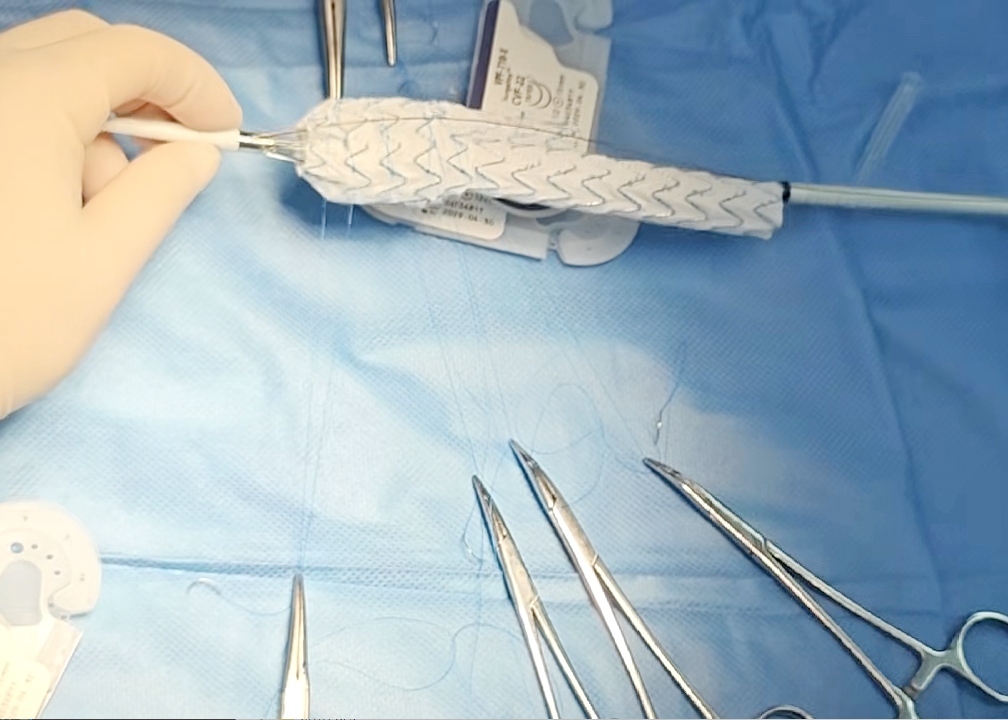

面对挑战,消化内科团队迅速启动多学科会诊。由血管外科驻桂专家王伦常博士、姚松良副主任医师及陈国兴硕士组成的攻坚小组,经全面评估后,决定优先通过微创手术处理动脉瘤。为了不影响后续的结肠手术,团队创新性地采用了PMEG技术,在局部麻醉下为患者施行了左侧髂内动脉瘤隔绝并重建术。术中,团队对支架进行了精准的台上改造与开窗,不仅成功隔绝了瘤体,更完美重建了左侧髂内动脉,保住了至关重要的血液供应。术后,患者恢复顺利,及时转入普外二病区(胃肠外科)完成了结肠肿瘤的治疗,现已康复出院。

术中团队对支架进行精准的台上改造与开窗

心脏问题解决后,治疗的“接力棒”交到了血管外科团队手中。团队预先在腹主动脉支架上为副肾动脉开窗并标记,随后在术中精准定位,将导丝导管通过开窗口超选入副肾动脉并成功植入支架,最终造影显示,腹主动脉瘤被完全隔绝,副肾动脉血流通畅,且无内漏。术后,患者肾功能维持良好,平安出院。

精准“束径”,为支架锚定与隔绝瘤体打下坚实基础

精细“开窗”,为副肾动脉预留生命的“侧门”

值得一提的是,这两例手术的核心——PMEG(医师改良腔内移植物)技术,被誉为血管外科的“定制裁缝”。它要求医生在手术台上,根据患者独特的血管解剖结构,对标准支架进行现场裁剪与开窗,实现“量体裁衣”式的精准治疗。作为处理累及内脏分支动脉的主动脉病变的先进微创方法,该技术主要在国家级和省级血管外科中心开展,桂林医院血管外科是广西为数不多可开展此类手术的科室。